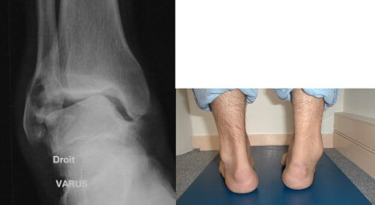

İnversiyon yaralanmaları sonucu oluşan bağ lezyonları instabiliteye neden olabilir. Ayak bileği instabilitesi,...

Talocrural eklem, karmaşık hareketler yapar. Maksimum stabilite, dorsifleksiyon + subtalar eklemde kalkaneal valgus...